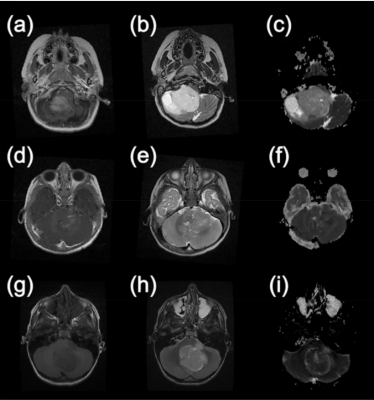

Brain Tumors In Children Nejm from www.nejm.org The first step in detecting a brain tumor is to recognize the symptoms. There are many different types of brain tumors. However, there have been significant advances in pediatric neurosurgery in of course, many children have challenges in these areas that have nothing to do with a brain tumor. Types, symptoms, diagnosis & treatment | world brain tumor day 2020on the occasion of world brain tumor day, dr. How to determine the cause of baby's brain damage. How will the biopsy results affect my treatment plan? What you really want to know is what are the odds that your infant has suffered brain damage? As the tumor grows, it creates pressure on and changes the function of surrounding brain.